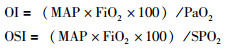

1.4 数据收集5例患儿的基本资料,ECMO建立前后的呼吸机参数、呼吸功能指标,ECMO建立的模式及持续时间,ECMO期间的并发症,及预后等数据被记录。OI和OSI通过以下公式计算得出:

|

其中MAP=平均气道压